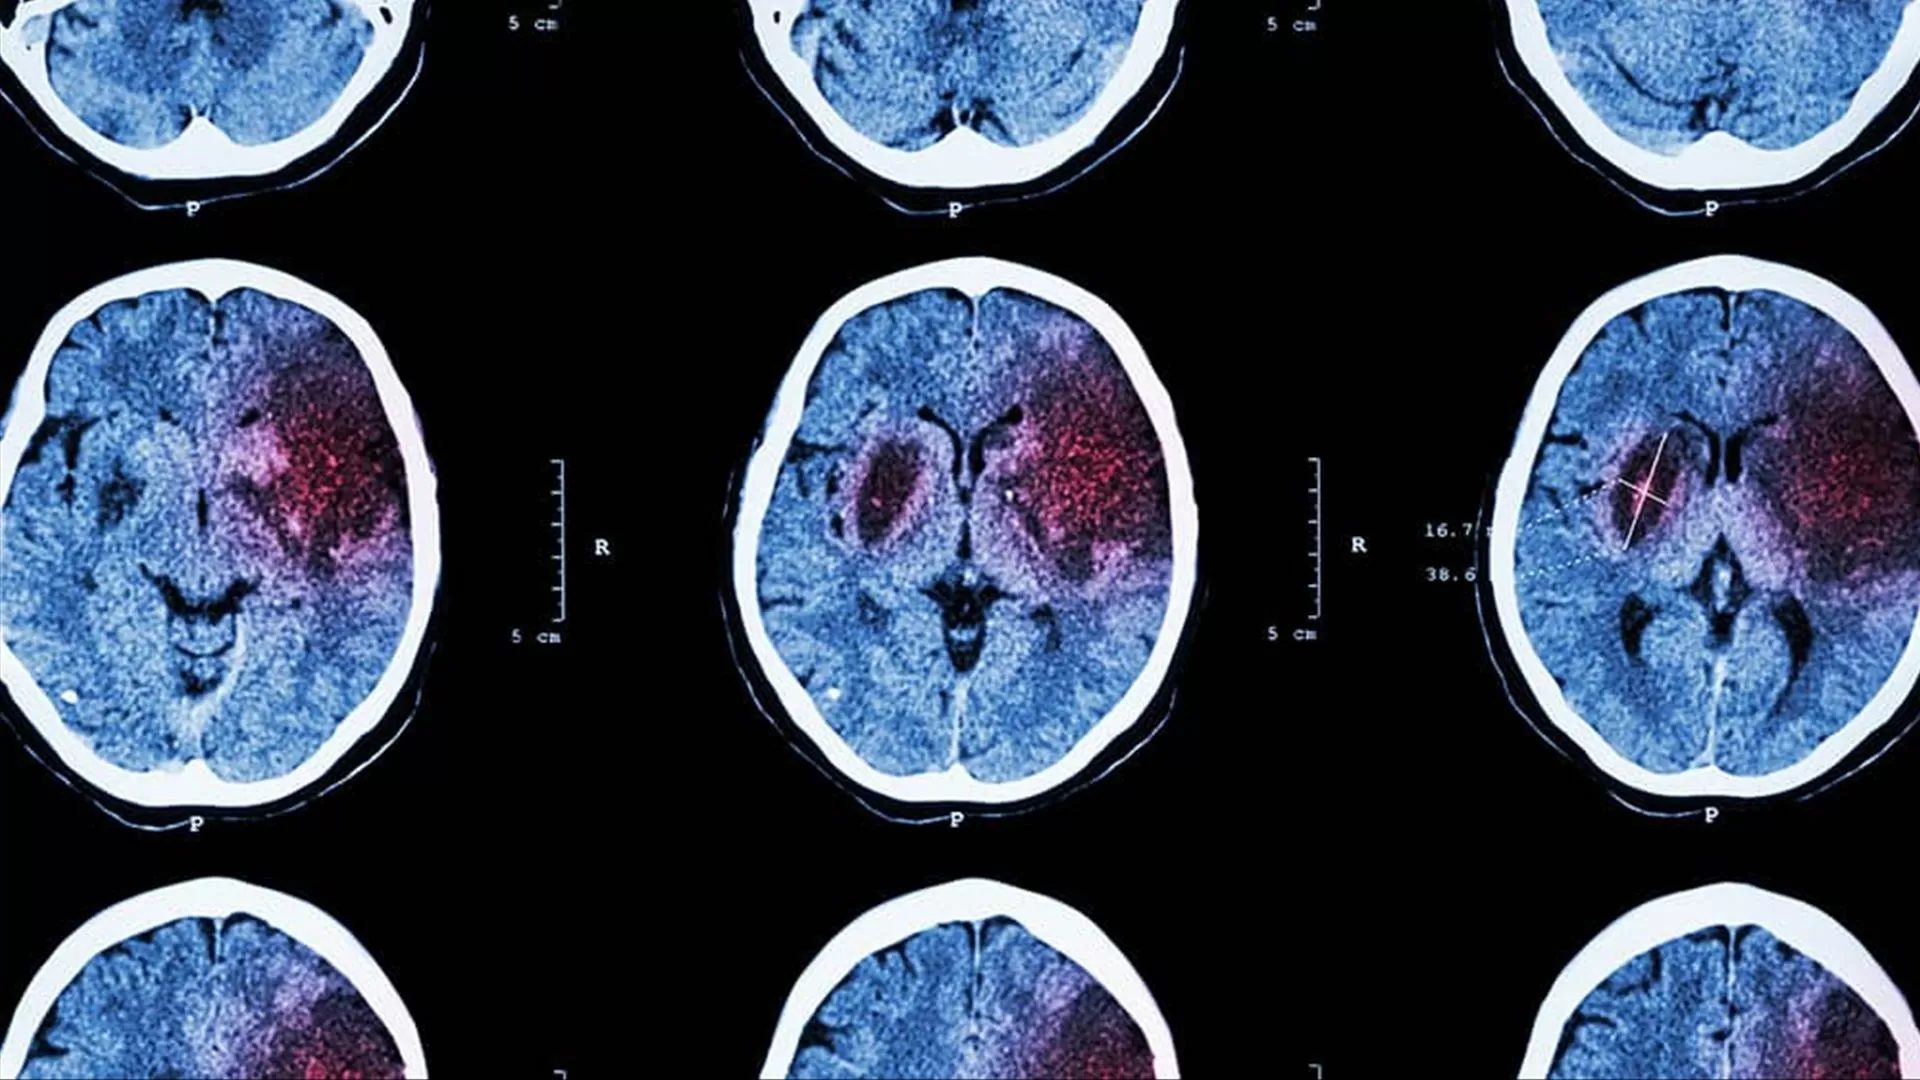

O estudo foi realizado em camundongos e mostrou que, após uma lesão cerebral, os macrófagos se movem para a área afetada e começam a produzir uma proteína chamada “GDF10”. Essa proteína é responsável por estimular a produção de novos neurônios, promovendo a regeneração do tecido cerebral danificado.

Além disso, o estudo também pode ter um impacto significativo no tratamento de lesões cerebrais traumáticas. Atualmente, não há uma forma eficaz de promover a regeneração de neurônios após uma lesão cerebral. No entanto, com a descoberta dos macrófagos como aliados na reparação cerebral, novas terapias podem ser desenvolvidas para ajudar na recuperação desses pacientes.